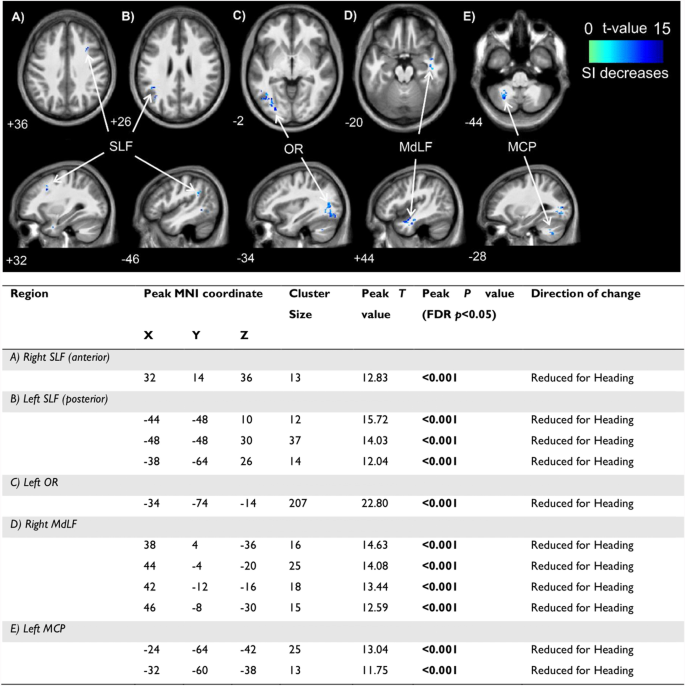

Heading significantly reduced tissue conductivity in 11 clusters located in the white matter of the frontal, occipital, temporal and parietal lobes, and cerebellum. The location, size and T values of these clusters are presented in Fig. 3. No significant increases in conductivity were observed.

Locations of significant clusters from electrical properties tomography data (above) and statistical details (below) between conditions in A right SLF (anterior); B left SLF (posterior); C left OR; D right MdLF; and E left MCP. Cooler (blue) colours represent higher t values and a decrease in signal intensity. Location of each sagittal and axial slice in Montreal Neurological Institute space are indicated at the bottom left of each slice. Abbreviations: MCP–middle cerebellar peduncle; MdLF–middle longitudinal fasciculus; MNI–Montreal Neurological Institute; OR–optic radiation; SI–signal intensity; SLF–superior longitudinal fasciculus